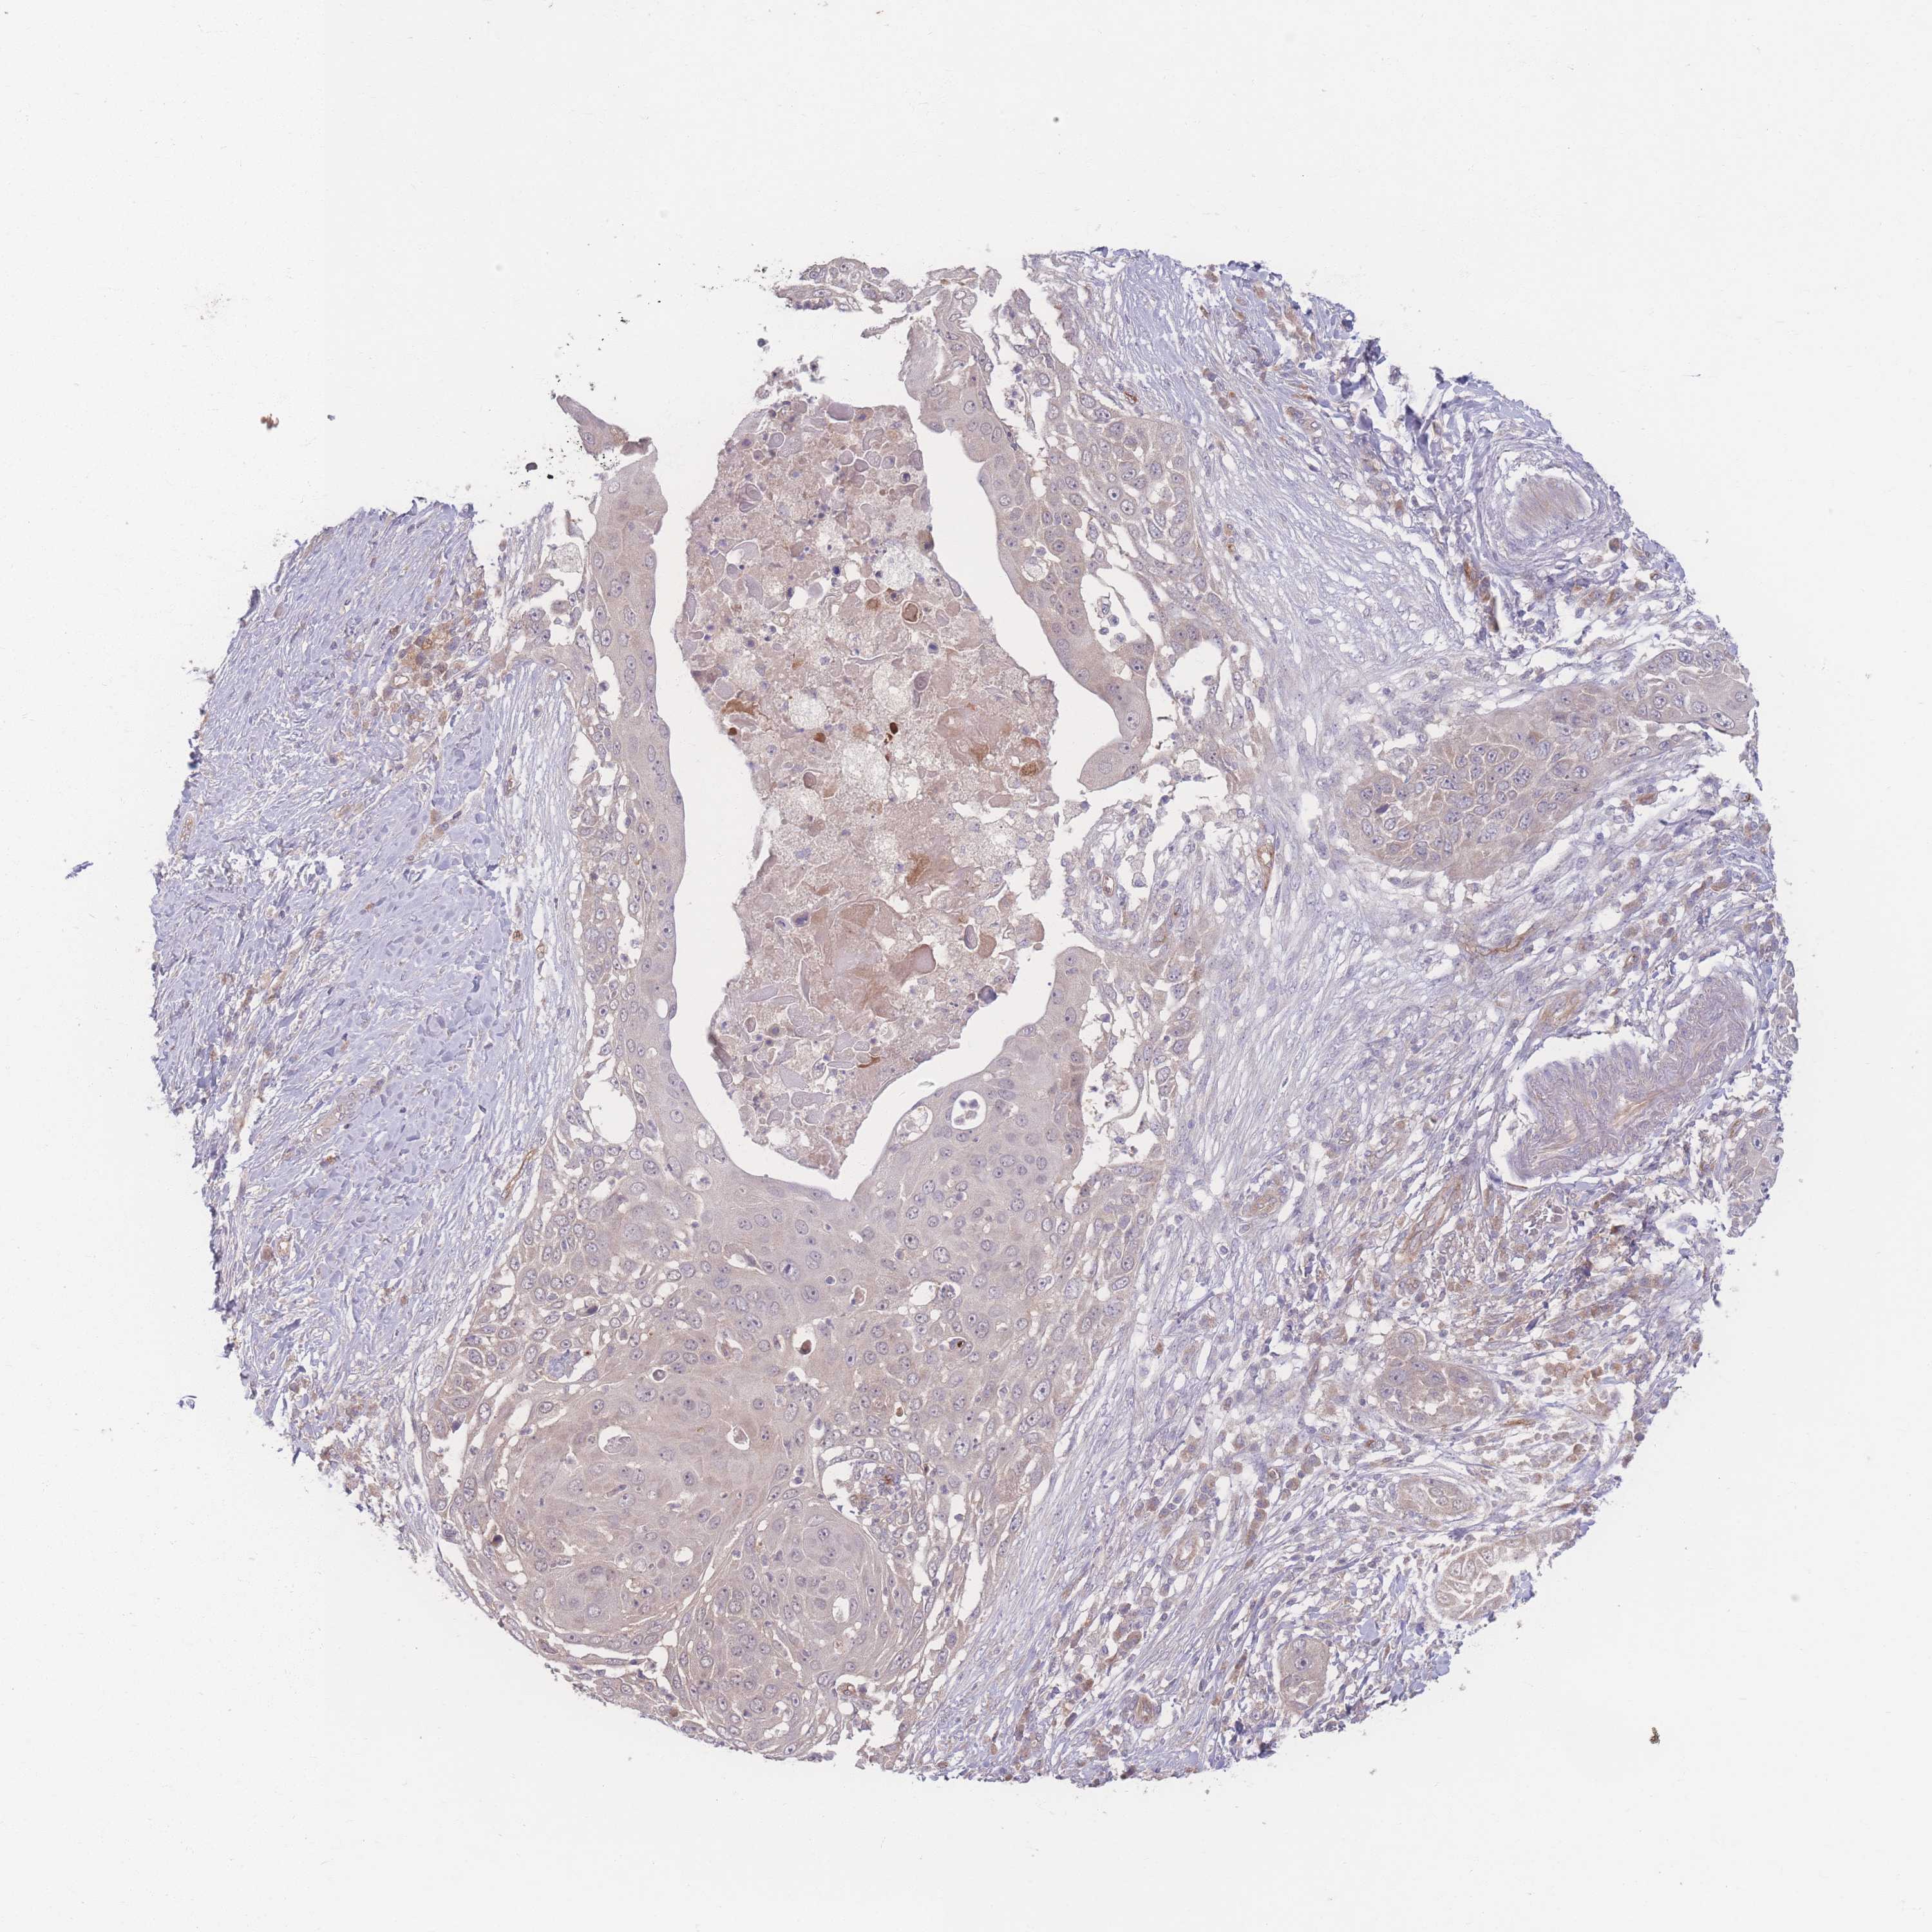

SKIN CANCER - Protein expressioni

A mouse-over function shows sample information and annotation data. Click on an image to view it in a full screen mode. Samples can be filtered based on level of antibody staining by selecting one or several of the following categories: high, medium, low and not detected. The assay and annotation is described here.

Antibody stainingi

Antibody staining in the annotated cell types in the current human tissue is reported as not detected, low, medium, or high, based on conventional immunohistochemistry profiling in selected tissues. This score is based on the combination of the staining intensity and fraction of stained cells.

Each image is clickable and will lead to virtual microscopy that enables deeper exploration of all samples and also displays staining intensity scores, fraction scores and subcellular localization as well as patient and tissue information for each sample.

Antibody HPA036302

Staining

High

Medium

Low

Not detected

Intensity

Strong

Moderate

Weak

Negative

Quantity

>75%

75%-25%

<25%

None

Location

Nuclear

Cytoplasmic/membranous

Cytoplasmic/membranous,nuclear

Basal cell carcinoma

Squamous cell carcinoma, NOS

Squamous cell carcinoma, metastatic, NOS